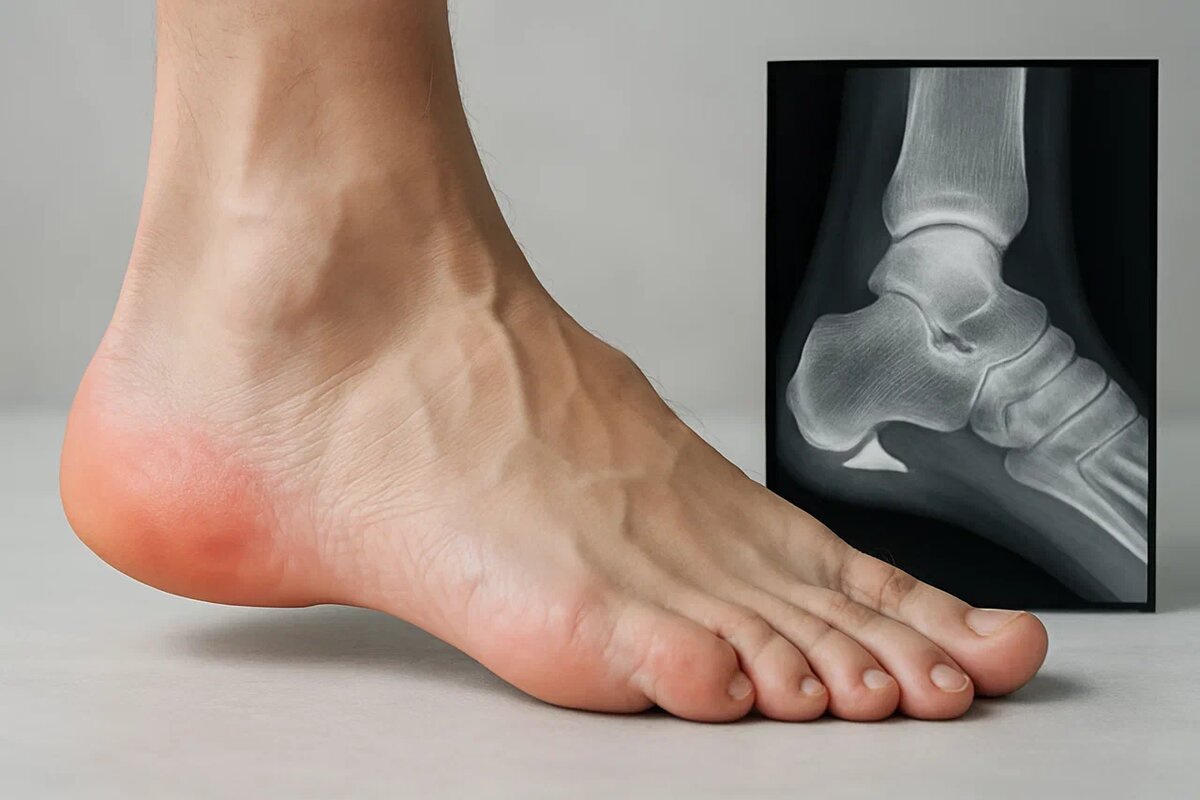

Пяточная шпора — это кальциевое уплотнение (остеофит), которое формируется на подошвенной поверхности пяточной кости. Звучит пугающе, но само по себе оно не болит. Многие люди имеют шпору, даже не подозревая об этом — она обнаруживается случайно на рентгене.

Настоящая проблема — плантарный фасциит. Это воспаление подошвенной фасции — плотной связки, которая тянется от пяточной кости до основания пальцев и поддерживает свод стопы. Когда эта связка перенапрягается, микротравмируется и воспаляется, возникает острая, «колющая» боль в пятке, особенно при первых шагах утром.

Шпора — лишь следствие этого процесса. Организм пытается «усилить» место постоянного напряжения, откладывая кальций. Но чем больше нагрузка, тем сильнее воспаление — и тем больнее становится ходить.